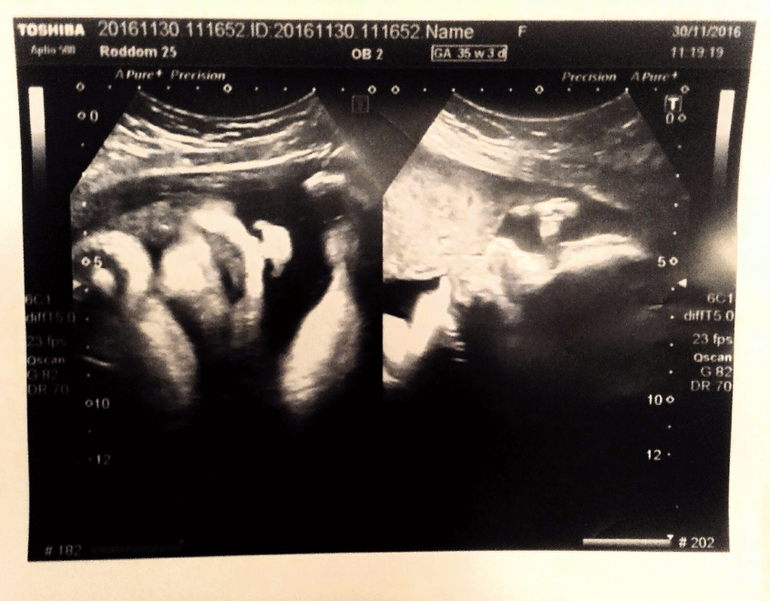

В среду ездила в роддом, на прием. Седлали нам УЗИ, на сроке 35+3 прошли мы прием и осмотр доктора. Все у нас хорошо, лежим правильно! Наш маленький хомячок уже 2800)))) Лежим низко, но головка еще в таз не стала. шейка короткая, но закрыта-сколько не сказали. УЗи наше началось так- ого, хорошая головка.... ооо, и щеки какие!!! первые роды? я-да! Доктор - повезло...! и ржет))) короче, нам перехаживать нельзя, совсем! даже пол часика! Иначе нашей булочки и щеки втянуть не поможет))) Все у нас соответствует 36 неделям, а голова на 39-40.....размером головы в папу, щеками в маму! ну сын своих родителей!))))

вот, наверное наше последнее фото с узи))) следущая фотка будет уже у мамы на ручках)))

Вот наш пирожок))) на левой фотке, он кокетливо прикрывает глазки ручкой, и нос курнос...и губки бантиком..... прям так и хочется громко так чмокнуть!)))) А на правой наш профиль)))